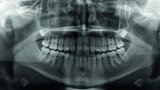

Orthodontic management of maxillary lateral incisors agenesis